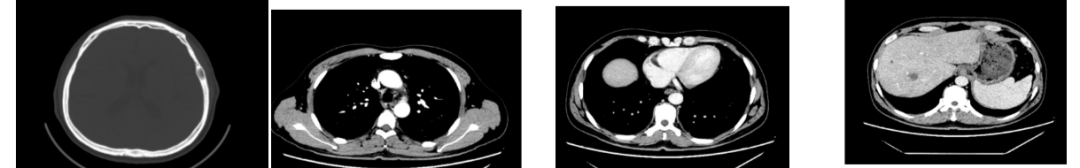

外院CT检查提示:1、两肺多发斑片状、结节影,性质待定,转移瘤?2、纵隔内多发肿大淋巴结;3、肝实质多发稍低密度影,性质待定(转移瘤可能性大)

2018-03-08 PET/CT示:胃癌(?)并全身多发淋巴结转移、肝脏多发转移、双肺上叶多发转移;

△2018-3-19基线CT

辅助检查

糖基抗原CA242>157.50U/mL;

糖基抗原CA724>300.00U/mL;

血常规、血生化:未见异常;

心脏超声:EF 78%;

二代测序结果:ERBB2拷贝数增加n=3.01(血浆)/n=3.02(新鲜组织)

KRAS及NRAS野生型、MET拷贝数增加n=8.79(血浆)/n=11.61(新鲜组织)

诊断:胃低分化腺癌合并肝、肺转移,并多发淋巴结转移HER2扩增